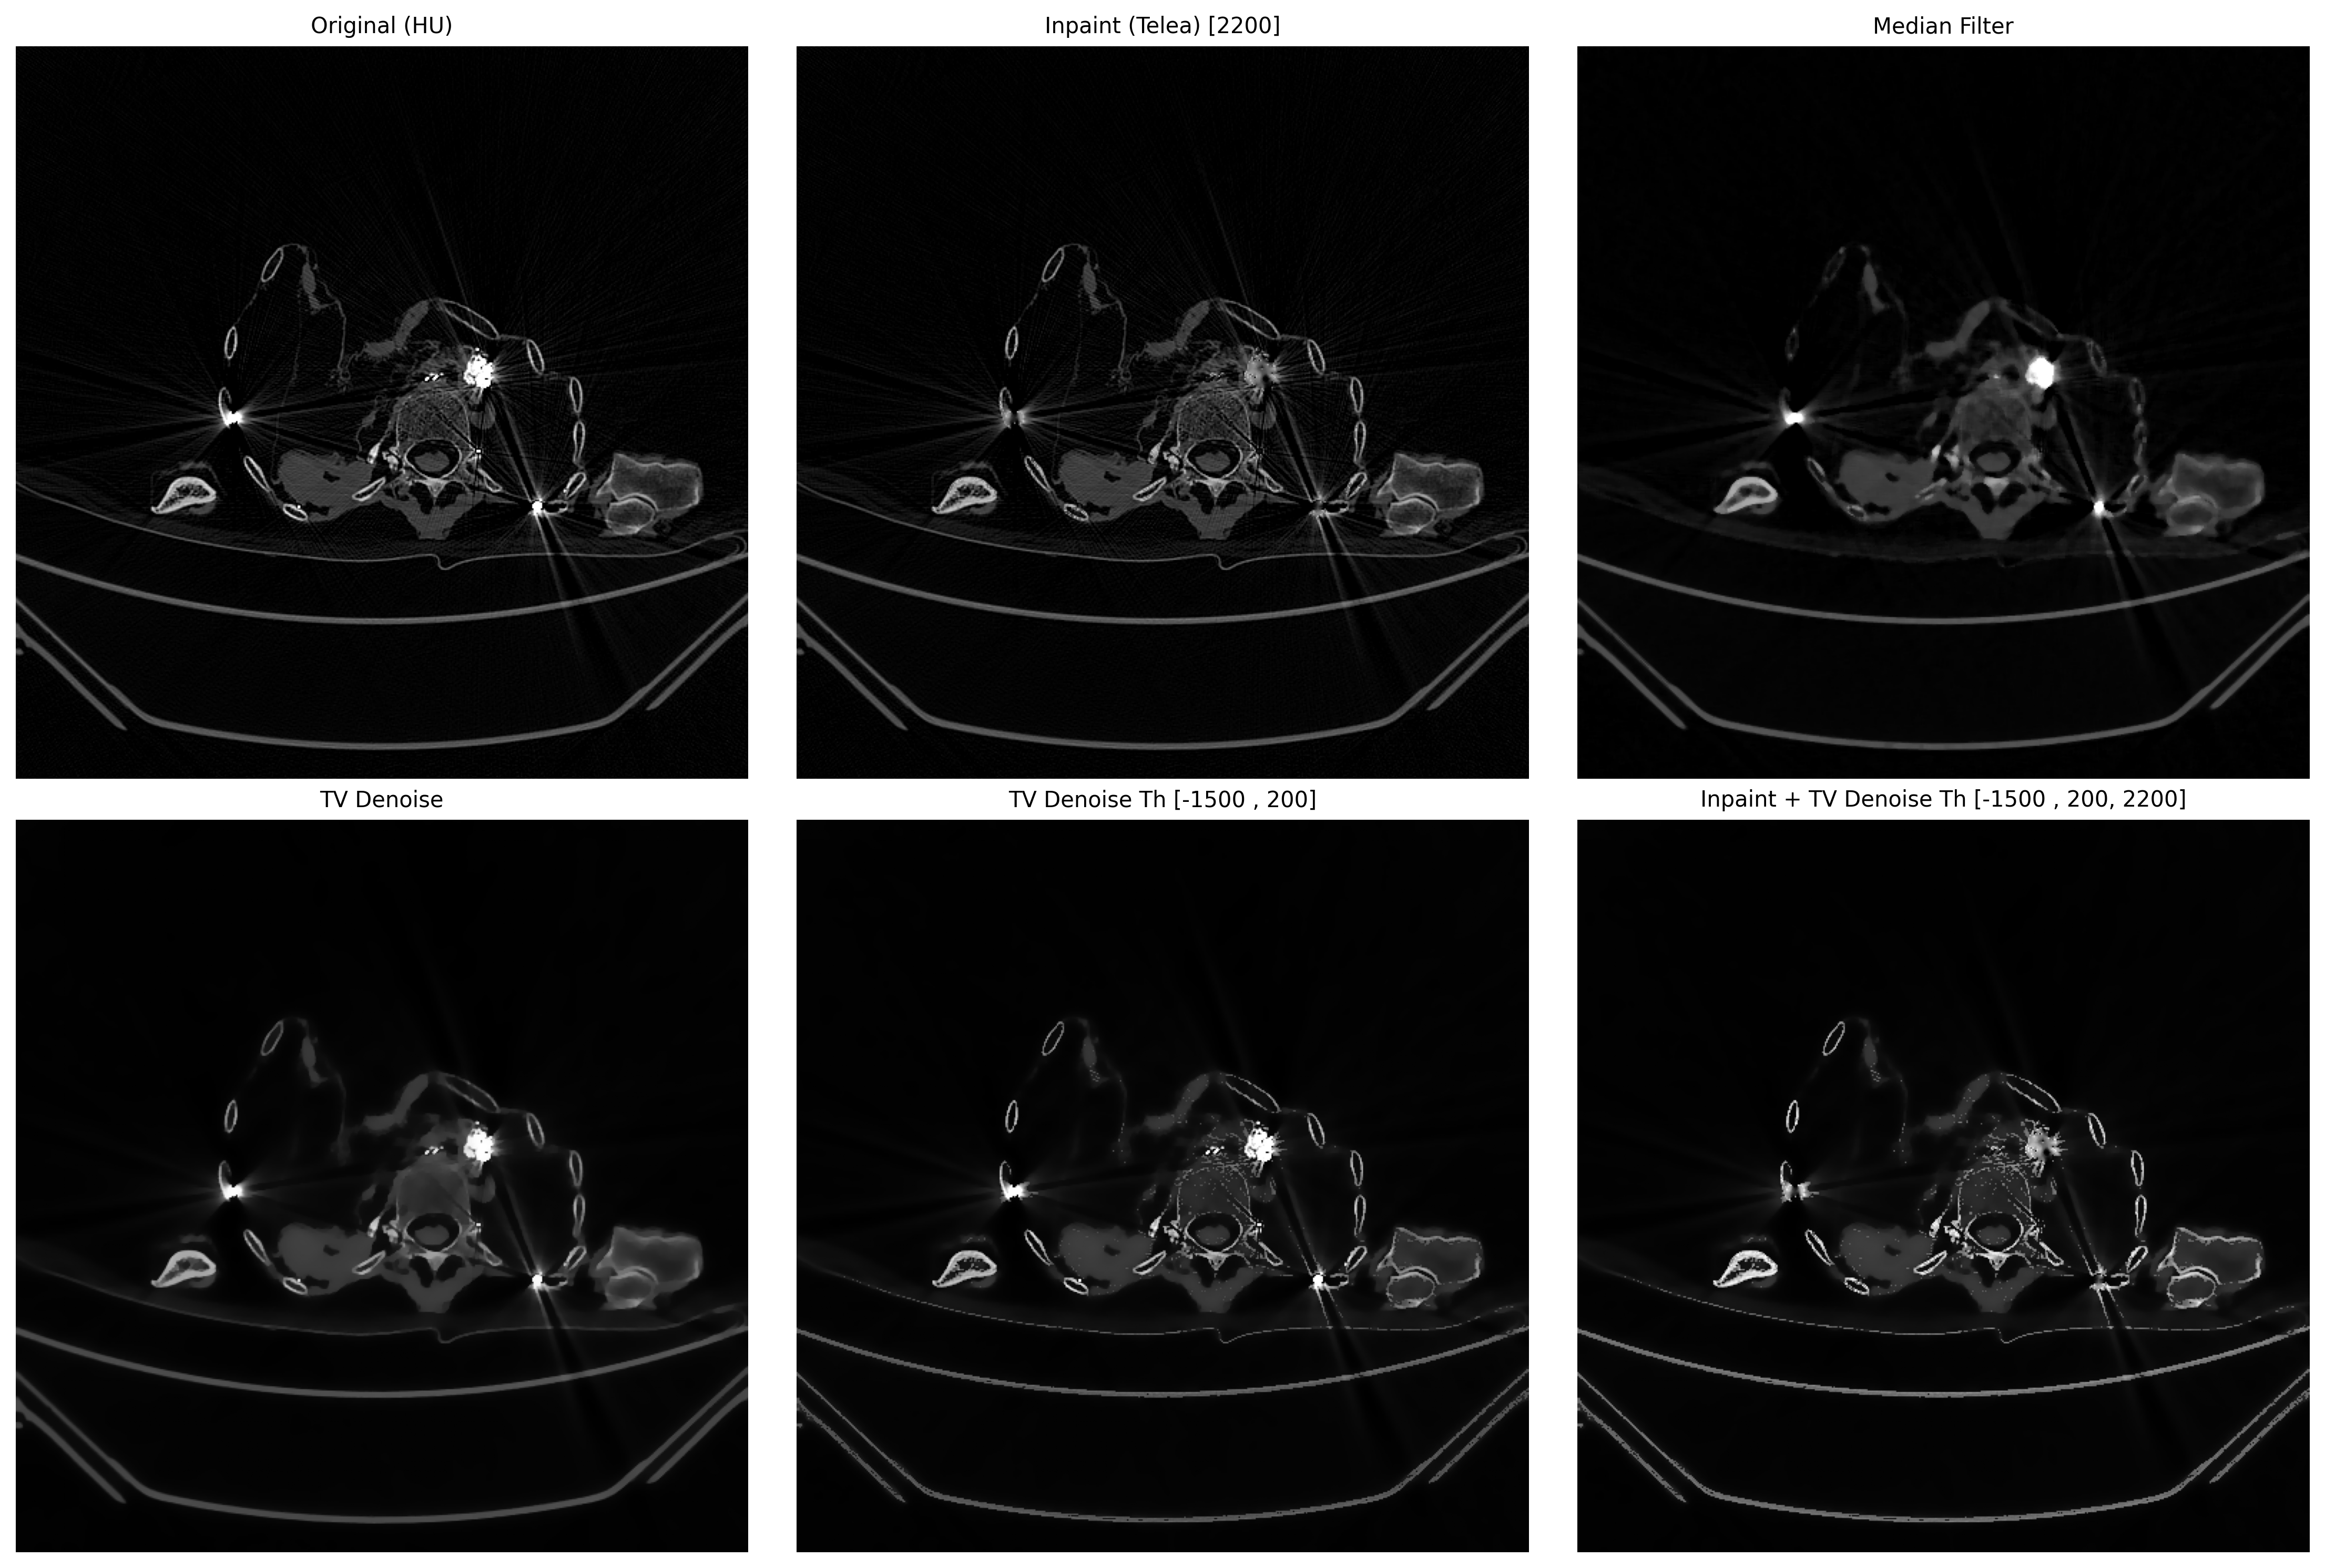

# 5. 汇总图

def create_summary(ct_hu, artifact, results, file_name):

fig, axes = plt.subplots(2, 3, figsize=(15, 10)) # 两行三列

axes = axes.ravel()

def show(i, img, title):

axes[i].imshow(img, cmap='gray', vmin=0, vmax=255)

axes[i].set_title(title, fontsize=10)

axes[i].axis('off')

# 0 号位:原图

show(0, exposure.rescale_intensity(ct_hu, out_range=(0, 255)),

"Original (HU)")

# 1 开始放 results

for idx, (name, img) in enumerate(results, start=1):

show(idx, img, name)

# 隐藏剩余空白子图

for j in range(len(results) + 1, 6):

axes[j].axis('off')

plt.tight_layout()

plt.savefig(f"metal_artifact_summary_{file_name}.png", dpi=300, bbox_inches='tight')

plt.show()

plt.close('all')

results = [

("Inpaint (Telea) [{}]".format(threshold), inpaint_opencv(ct_hu, mask)),

("Median Filter", median_filter(ct_hu)),

("TV Denoise", denoise_tv(ct_hu)),

("TV Denoise Th [{} , {}]".format(hu_min, hu_max), denoise_tv_th(ct_hu, hu_min=hu_min, hu_max=hu_max)),

("Inpaint + TV Denoise Th [{} , {}, {}]".format(hu_min, hu_max, threshold), inpaint_denoise_tv_th(ct_hu, hu_min=hu_min, hu_max=hu_max, threshold=threshold)),

]

create_summary(ct_hu, ct_hu, results, file_name)

Inpaint能去除金属,拖影使用TV Denoise。

其他案例,但需要更具直方图就行调整。